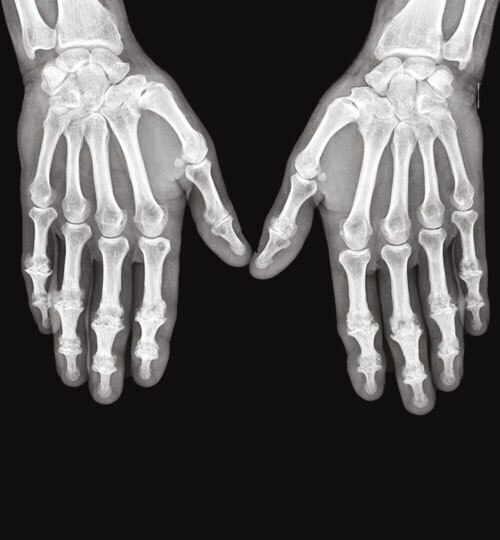

L’arthrose digitale des doigts longs évolue souvent par crises douloureuses et peut se distinguer par des signes inflammatoires locaux, en regard des articulations concernées, notamment dans sa forme érosive (figures). Un discret épanchement synovial peut être palpé, essentiellement au niveau des IPP, tandis que les kystes mucoïdes se développent surtout aux dépens des IPD. À un stade avancé, certaines articulations IPD sont le siège d’une laxité latérale, liée aux érosions osseuses et à la distension capsuloligamentaire. Des nodosités d’Heberden (IPD) et de Bouchard (IPP) peuvent être palpées : elles correspondent à l’ostéophytose du pourtour de l’articulation arthrosique. Une évolution vers l’ankylose des articulations distales est possible, à l’origine d’une déformation en position vicieuse et/ou d’un défaut de flexion, qui gênent considérablement la préhension.

La prévalence radiographique est supérieure à celle symptomatique

Dans la cohorte de Rotterdam (n = 3 906), la prévalence radiologique de l’arthrose digitale a été estimée chez les patients de plus de 55 ans : 67 % des femmes et 54,8 % des hommes inclus avaient au moins une articulation arthrosique. Les articulations les plus concernées étaient : les interphalangiennes distales (47,3 %), la trapézométacarpienne (35,8 %), les interphalangiennes proximales (18,2 %), puis les métacarpophalangiennes (8,2 %). Au cours de la vie, le risque de développer une arthrose digitale est de 47 % chez les femmes et de 24 % chez les hommes aux États-Unis.